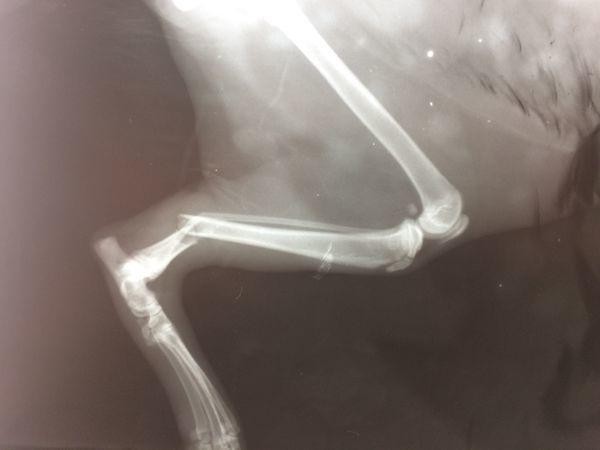

Перелом

Перелом – это нарушение целостности кости. Он сопровождается повреждением окружающих тканей. Возникают в результате травм.Чаще всего кошки ломают конечности, челюсти, ребра, хвост и таз. Закрытый перелом – кожные покровы в месте перелома не поврежденыОткрытый перелом – когда в месте перелома есть рана, из которой может быть видна кость.

Симптомы:Не могут шевелить травмированной частью телаНе могут опираться на травмированную частьБольОтекНеестественное положение части телаКровотечениеПри переломе ребер – сложно дышатПри переломе челюсти - слюнотечение

Первая помощь:Если перелом открытый – постарайтесь остановить кровь с помощью полотенца или марли. Обездвижьте травмированную часть тела.Отвезите к ветеринару.Лечение:Проводят операцию. Устанавливают специальные спицы в кости. Постепенно кости срастаются.